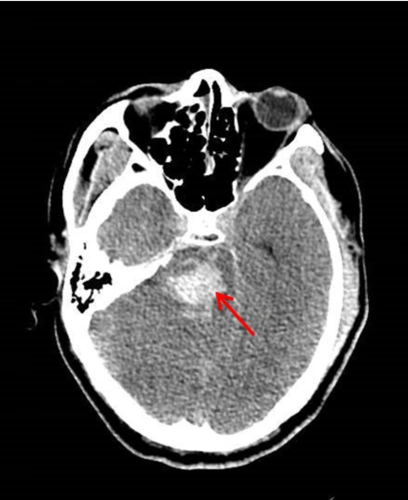

术前颅脑ct可见脑干出血.